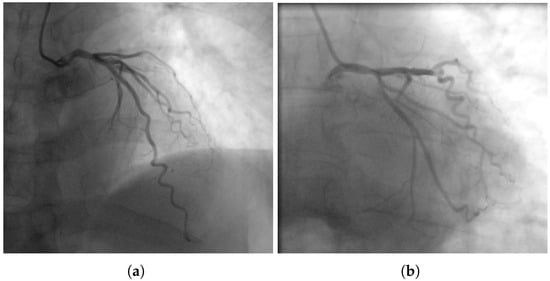

The Great Masquerader: Vasospastic Angina Mimicking Left Main Coronary Artery Disease

A significant proportion of patients undergoing invasive coronary angiography for angina have no obstructive coronary artery disease (CAD). In such patients, coronary microvascular dysfunction (CMD) and vasospastic angina (VSA) represent key pathophysiological mechanisms. We report a case of a 58-year-old male with exertional [...] Read more.

A significant proportion of patients undergoing invasive coronary angiography for angina have no obstructive coronary artery disease (CAD). In such patients, coronary microvascular dysfunction (CMD) and vasospastic angina (VSA) represent key pathophysiological mechanisms. We report a case of a 58-year-old male with exertional chest pain and exercise ECG changes typical of left main or multivessel CAD. Coronary computed tomography angiography (CCTA) showed borderline stenosis of the distal left main coronary artery. Coronary angiography revealed no critical stenosis. A comprehensive functional assessment demonstrated reduced coronary flow reserve (CFR = 2.0) and an elevated index of microcirculatory resistance (IMR = 25), consistent with CMD. An intracoronary acetylcholine provocation test induced severe focal vasospasm of the mid-left anterior descending artery (LAD) with ST-segment elevation and anginal pain, promptly relieved by nitroglycerin, confirming VSA. This case highlights the diagnostic and clinical importance of invasive functional testing in patients with angina and non-obstructive coronary arteries (ANOCA/INOCA). The coexistence of CMD and VSA (two distinct but overlapping pathophysiological endotypes) is increasingly recognized as a marker of adverse prognosis. Functional coronary assessment should be considered in all patients with angina and non-obstructive coronary arteries, as identifying mixed endotypes enables precise, mechanism-guided therapy. Full article